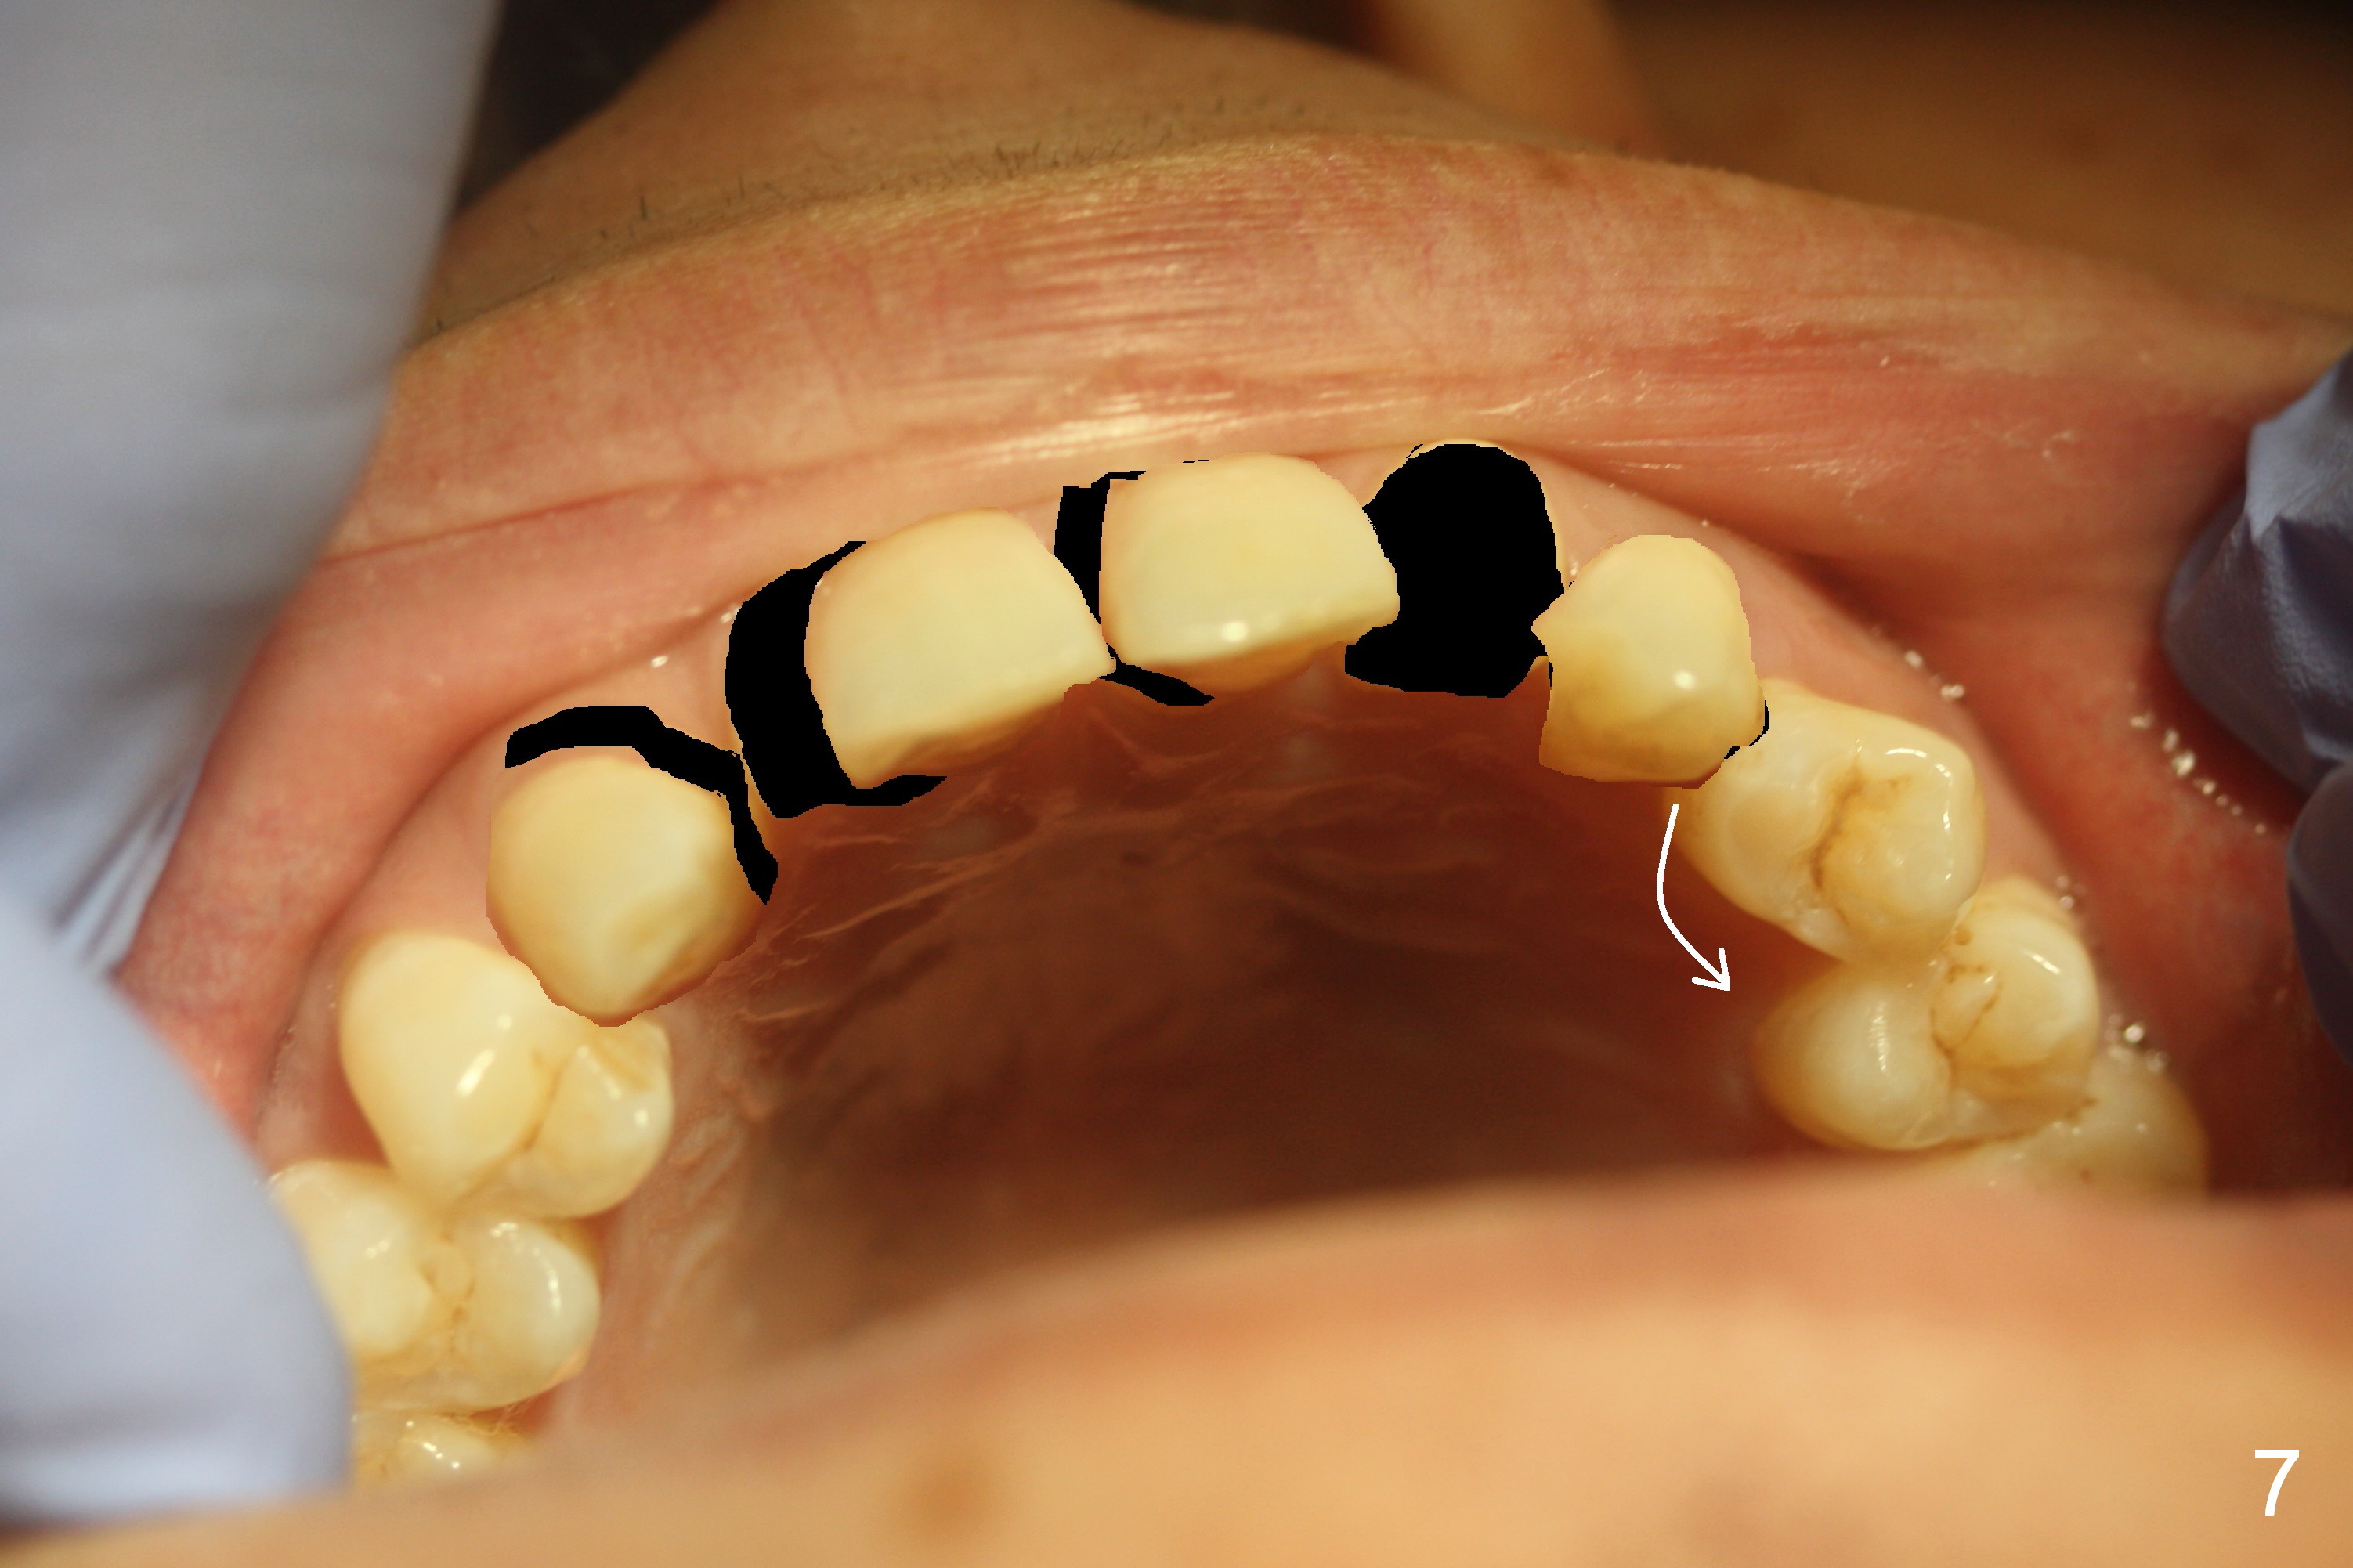

A 38-year-old man has congenitally missing laterals (Fig.1,2) with retention of a deciduous canine (Fig.2,3 C). UL 4 (upper left 1st bicuspid) rotates (Fig.3). LR7 has been extracted (Fig.4).